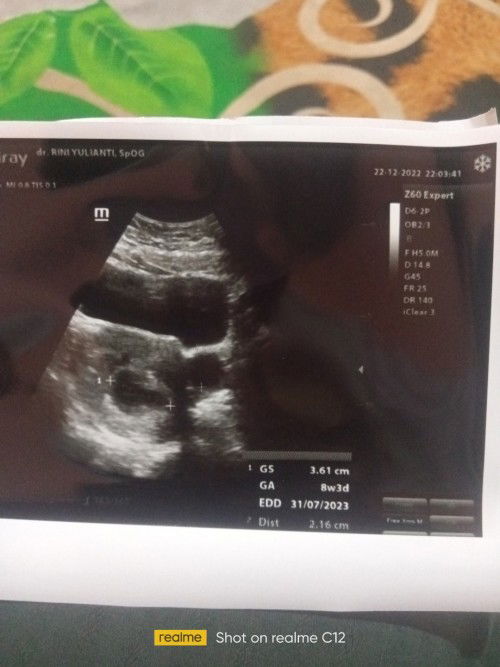

Hamil 8 minggu masih kantung dan ada kista

bunda mau sharing, ini aku habis usg ke 2 , yang pertama waktu 4 minggu, masih klihatan kantung dan normal tidak ada kista, trus kmaren usg lagi sudah masuk 8 minggu tapi masih kantung ukuran kantung normal, belum ada janin kata dokter dan ada kista 😭 disuruh balik lagi 2 minggu, bingung banget jadi pikiran juga, penantian sudah hampir 3 tahun 😭, ada yang pernah ngalamin gak bun? 🥺#bantusharing